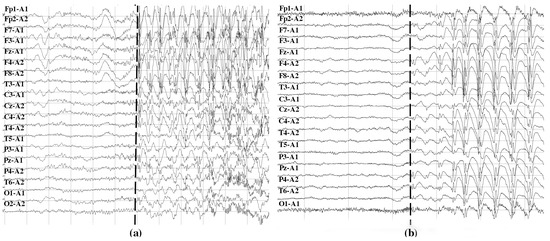

In total, 45 episodes of focal seizures and 22 episodes of generalized seizures were monitored. In patients with focal seizures, an average of 2.5 seizures per patient was analyzed (range: 1–8). In patients with generalized seizures, the average number of seizures analyzed per patient was 3.8 (the range was 1–3 in four patients, while the fifth exhibited 13 seizures). Signals were recorded at a sampling rate of 250 Hz by scalp electrodes placed according to the International 10/20 monopolar scheme, with the reference electrode placed on the ipsilateral ear. During the study, the acquisition of EEG signals was accompanied by continuous video monitoring to identify clinical events. In order to define the start and stop time of each seizure, the episode onsets were labeled in the EEG by qualified neurologists based on visual analysis of EEG data and video recordings as the events of the start of clinical appearance of an actual seizure. Figure 3 shows an example of EEG signals containing the start of focal (Figure 3a) and generalized (Figure 3b) seizures marked with dashed lines.

Preprocessing consisted in downsampling each signal to 125 Hz, followed by application of a bandpass filter (zero-phase IIR Butterworth filter) with cutoff frequencies at 0.5 Hz and 42 Hz. Only stationary EEG trials without noticeable artifacts were manually selected for the analysis. The EEG time series were then normalized to zero mean and unit variance before calculating information theoretic measures. More details on data acquisition and pre-processing are given in previous studies [40,41].